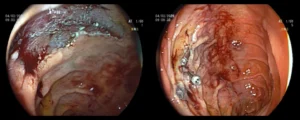

Πολύποδας δωδεκαδακτύλου

![]()